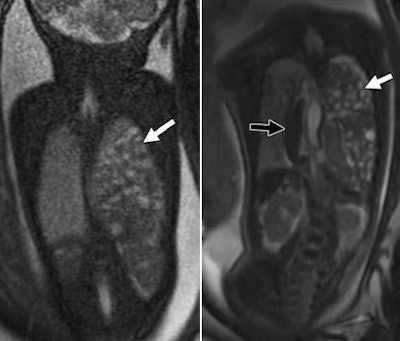

Collectively, 3-tesla MRI with SSFP sequences achieved higher quality scores than 1.5-tesla MRI with the same sequence for most structures, especially the bowel, liver, lungs, kidneys, cartilage, and spine. Both readers rated 3-tesla MRI as only "marginally better" than 1.5-tesla imaging of the airway.

"The gain is really with the true SSFP," Victoria said. "The depiction of the kidneys is magnificent when you look at it with 3 tesla, and you can see the lungs in much greater detail."